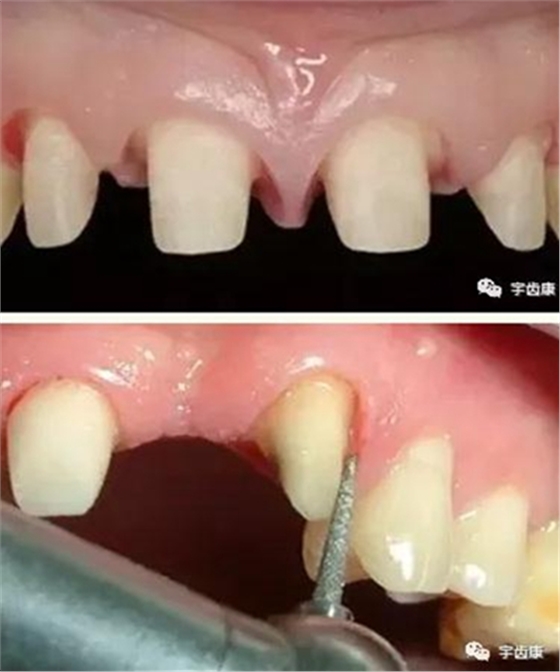

實際備牙產(chǎn)生的問題

8. 實際備牙產(chǎn)生的問題

牙體預(yù)備時需注意的問題

預(yù)備時注意的問題